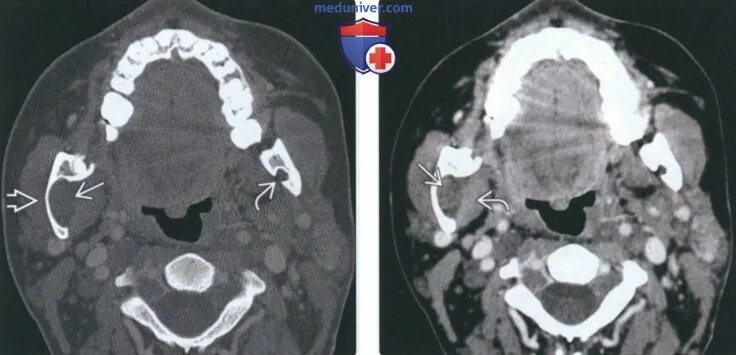

Нейрофиброматоз мрт